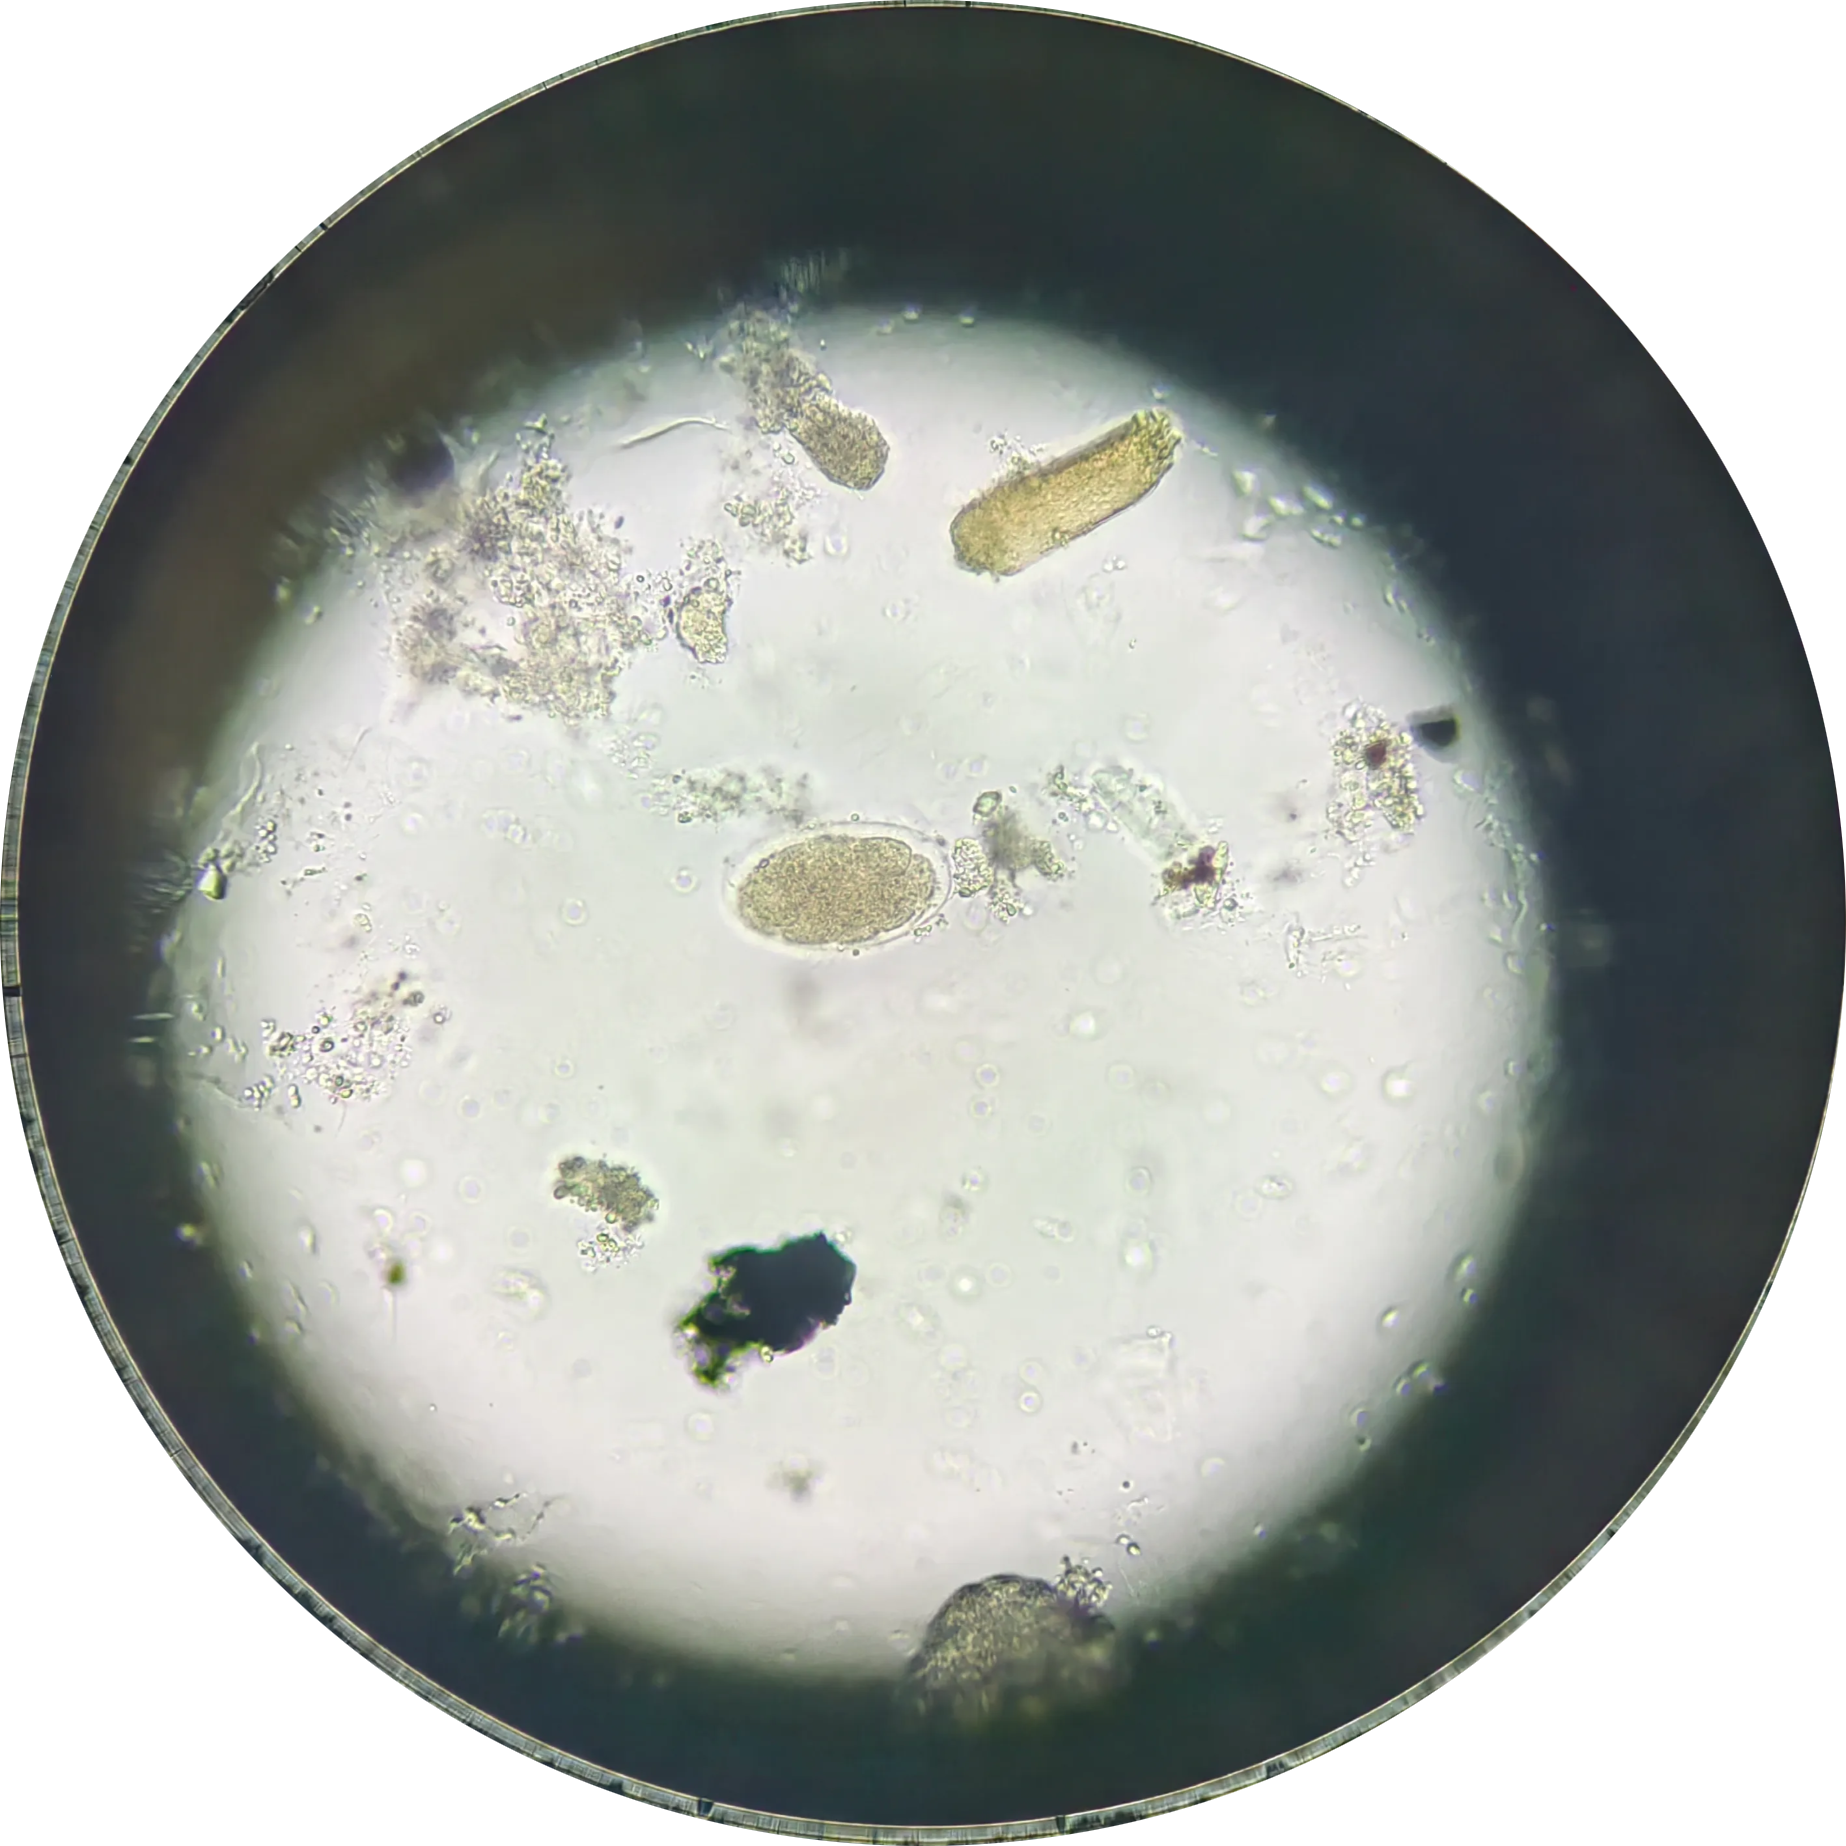

钩虫卵

💡

钩虫卵 壳薄,透明,多细胞,间隙明显

椭圆形,大小(57~76)μm× (36~40)μm,两端钝圆。卵壳较薄, 无色透明,卵内通常含2~4个卵细胞, 卵壳与卵细胞之间有明显空隙。在便秘者粪便内或粪便放置过久时,卵内细胞可继续分裂成桑葚状。两种钩虫卵形态相似,不易区别。